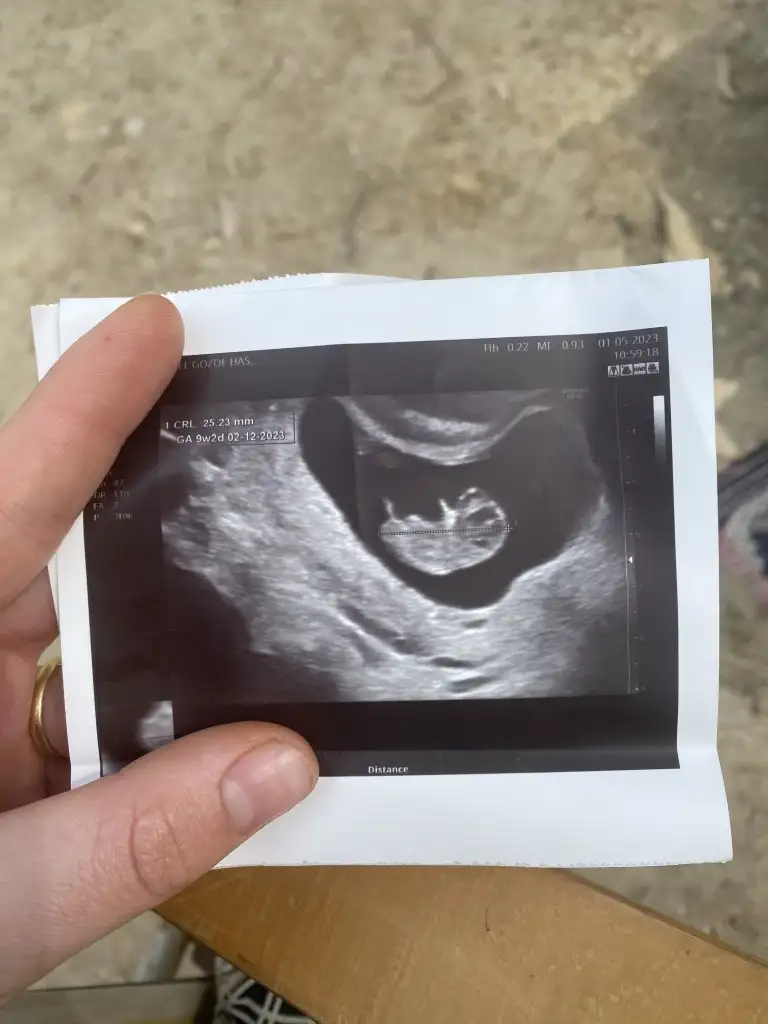

Selam kızlar ben kontrolden geldim her şey yolunda çok şükür burun kemiği ve ense kalınlığı normal yarın nift için kan vercem ☺️ giderken bir kare çikolata yedim beniş o kadar haraketliydi ki o yüzden düzgün bi fotoğrafı yok😂😂 videodan görüntü aldım onu atıyorum. Tahminler kızdı ama doktor bacak arasında çıkıntı gördü resimde okla gösterilen yere bakın 🙈 ilk resimde de eli havada 😍Eki Görüntüle 3242883 Eki Görüntüle 3242884